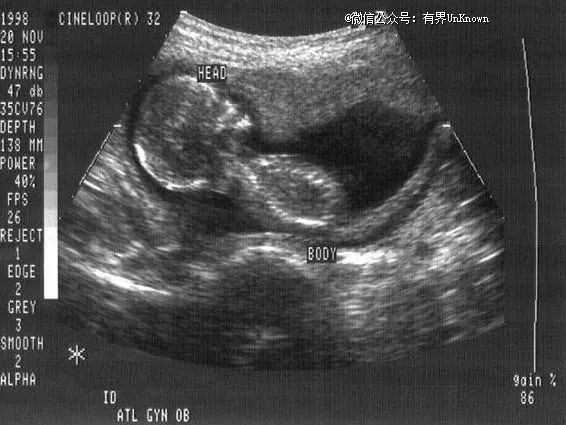

▲ 孕妇怀孕期间的B超图像